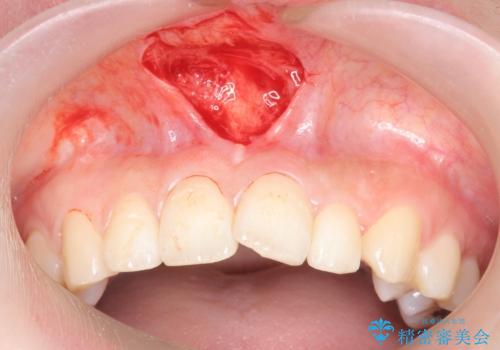

上唇小帯切除

- 他院で矯正のカウンセリングに行ったところ

上唇小帯の付着位置が前歯に近くて矯正ができないと言われて来院。

矯正を行なっても後戻りのリスクが高いので、上唇小帯の切除を行いました。